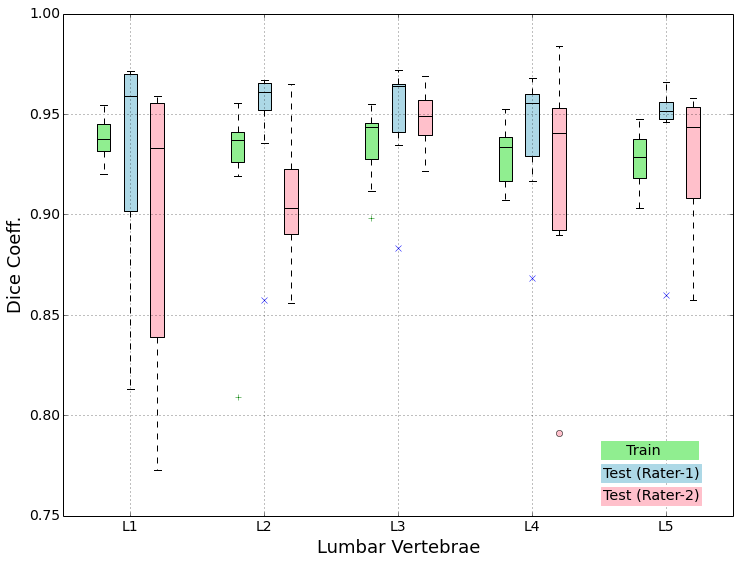

The segmentation network is implemented in the Caffe framework. A cross-entropy loss is optimised using an Adam solver with an initial learning rate of 1e-4. The binary segmentation network is run for 3000 epochs and the multi-class segmentation (with pre-training) net was run for 2000 epochs. The segmented bounding boxes are reinstated into the actual volumes to obtain the full-resolution segmentations. We report the Dice coefficient for each of the five vertebrae and for the entire lumbar region in table 2. The evaluation is carried out based on the available ground truth segmentations of the train set and those from both Rater-1 and Rater-2 in case of the test set. We also observe a mean Dice score of 92%. Since our segmentation is the starting point for Rater-1, a bias in the corresponding performance scores can be observed, with a mean Dice score of 94%. Figure 3 shows the spread of the Dice coefficients across vertebrae and among the datasets. Observe that the vertebrae in the middle (L3 and L4) are segmented well compared to the peripheral vertebrae (L1 and L5). This is expected since the uncertainty that the net has to overcome for deciding between L1 & T12 or L5 & S1 is higher compared to deciding between L2 & L3 or L3 & L4 owing to the large receptive field etc.

In general, both the stages in our pipeline work remarkably well as per the quantitative results in tables 1 and 2. We obtain a near perfect localisation of 1.0 for almost every case, and a mean Dice score of 92%. In addition to this, the prime motivation of our approach is to successfully segment the deformed spines where the model-based approaches fail. This can be observed visually in figure 4. Four test cases as shown highlighting the highly deformed spine and vertebrae. Observe that our algorithm successfully segments these cases in spite of the severe deformations.